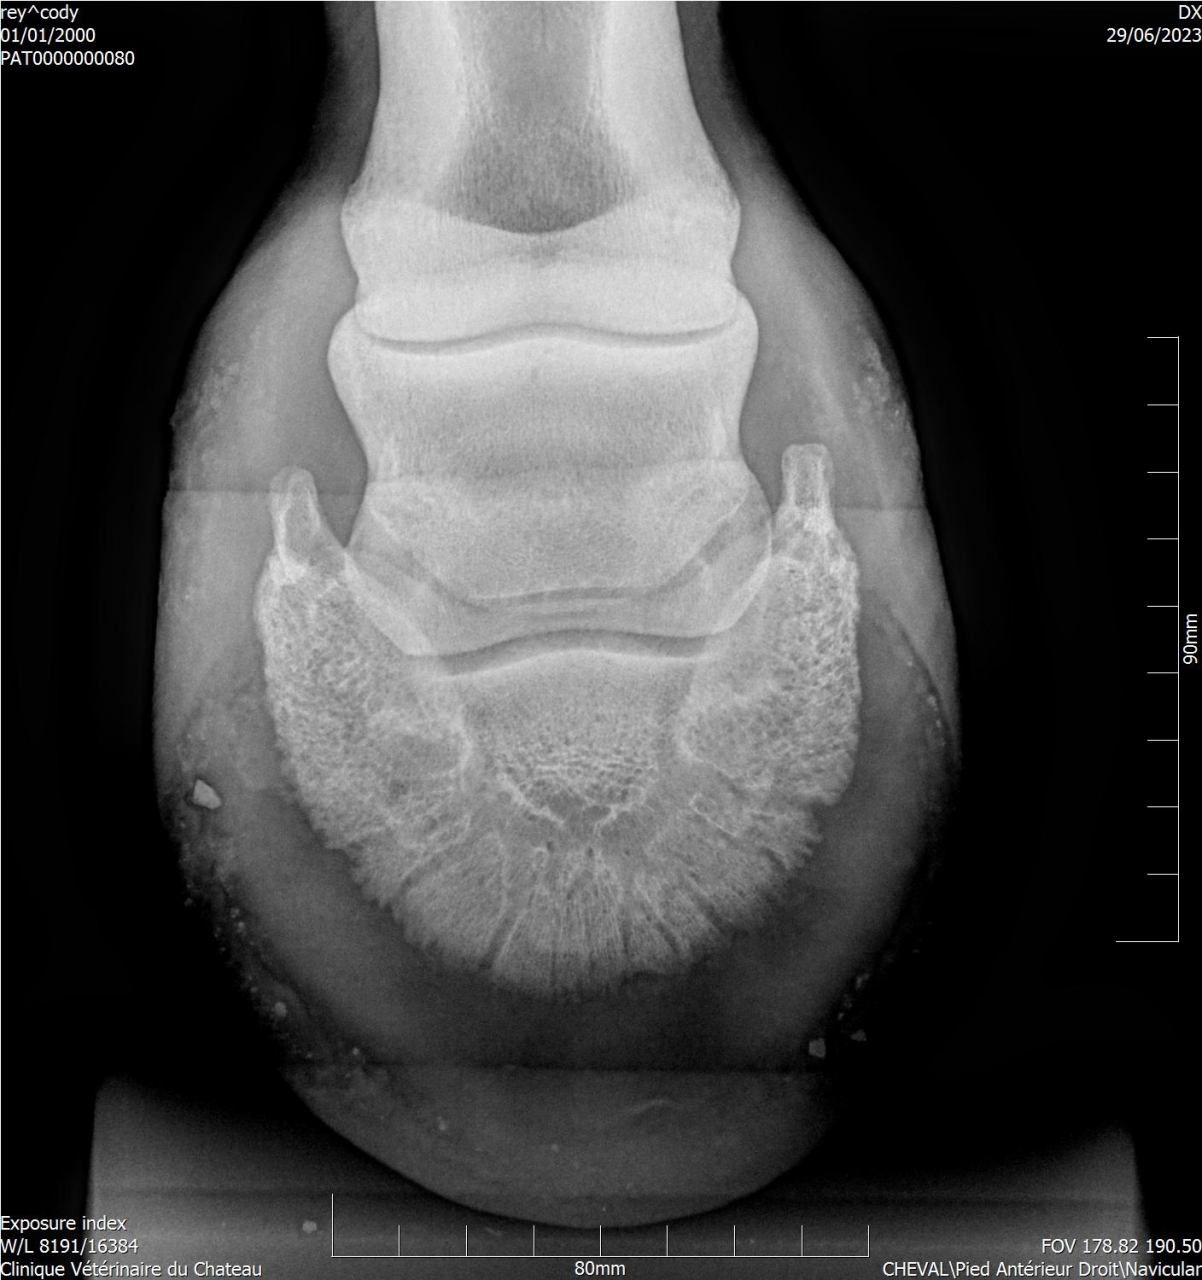

Par goss_de_panloup : le 02/11/24 à 20:39:15

| Dire merci | Aucun des vétos consultés n’a été capable de donner une explication à la boiterie et à la douleur au ferrage ... Voici des radios de l’année dernière : ![]() ![]() Si quelqu'un a une bonne adresse de spécialiste en Isère je prends. |

| Dire merci | Tu as une radio LM par hasard ? |

| Dire merci | Un cheval qui bosse pas, qui a juste 10 ans et qui a une locomotion dégradée selon les jours, ça pue l arthrose précoce, le naviculaire ou chais pas quoi. Il te faut un vrai bilan ds une clinique qui sait faire les radios et échos et qui sait les lire |

| Dire merci | Voir aussi que beaucoup d'américains ont des problèmes de pieds. Je me dis qu'en allant faire un bilan locomoteur plus poussé dans une clinique, tu auras aussi plus de gens d'avoir des vétos qui connaissent ces problèmes |